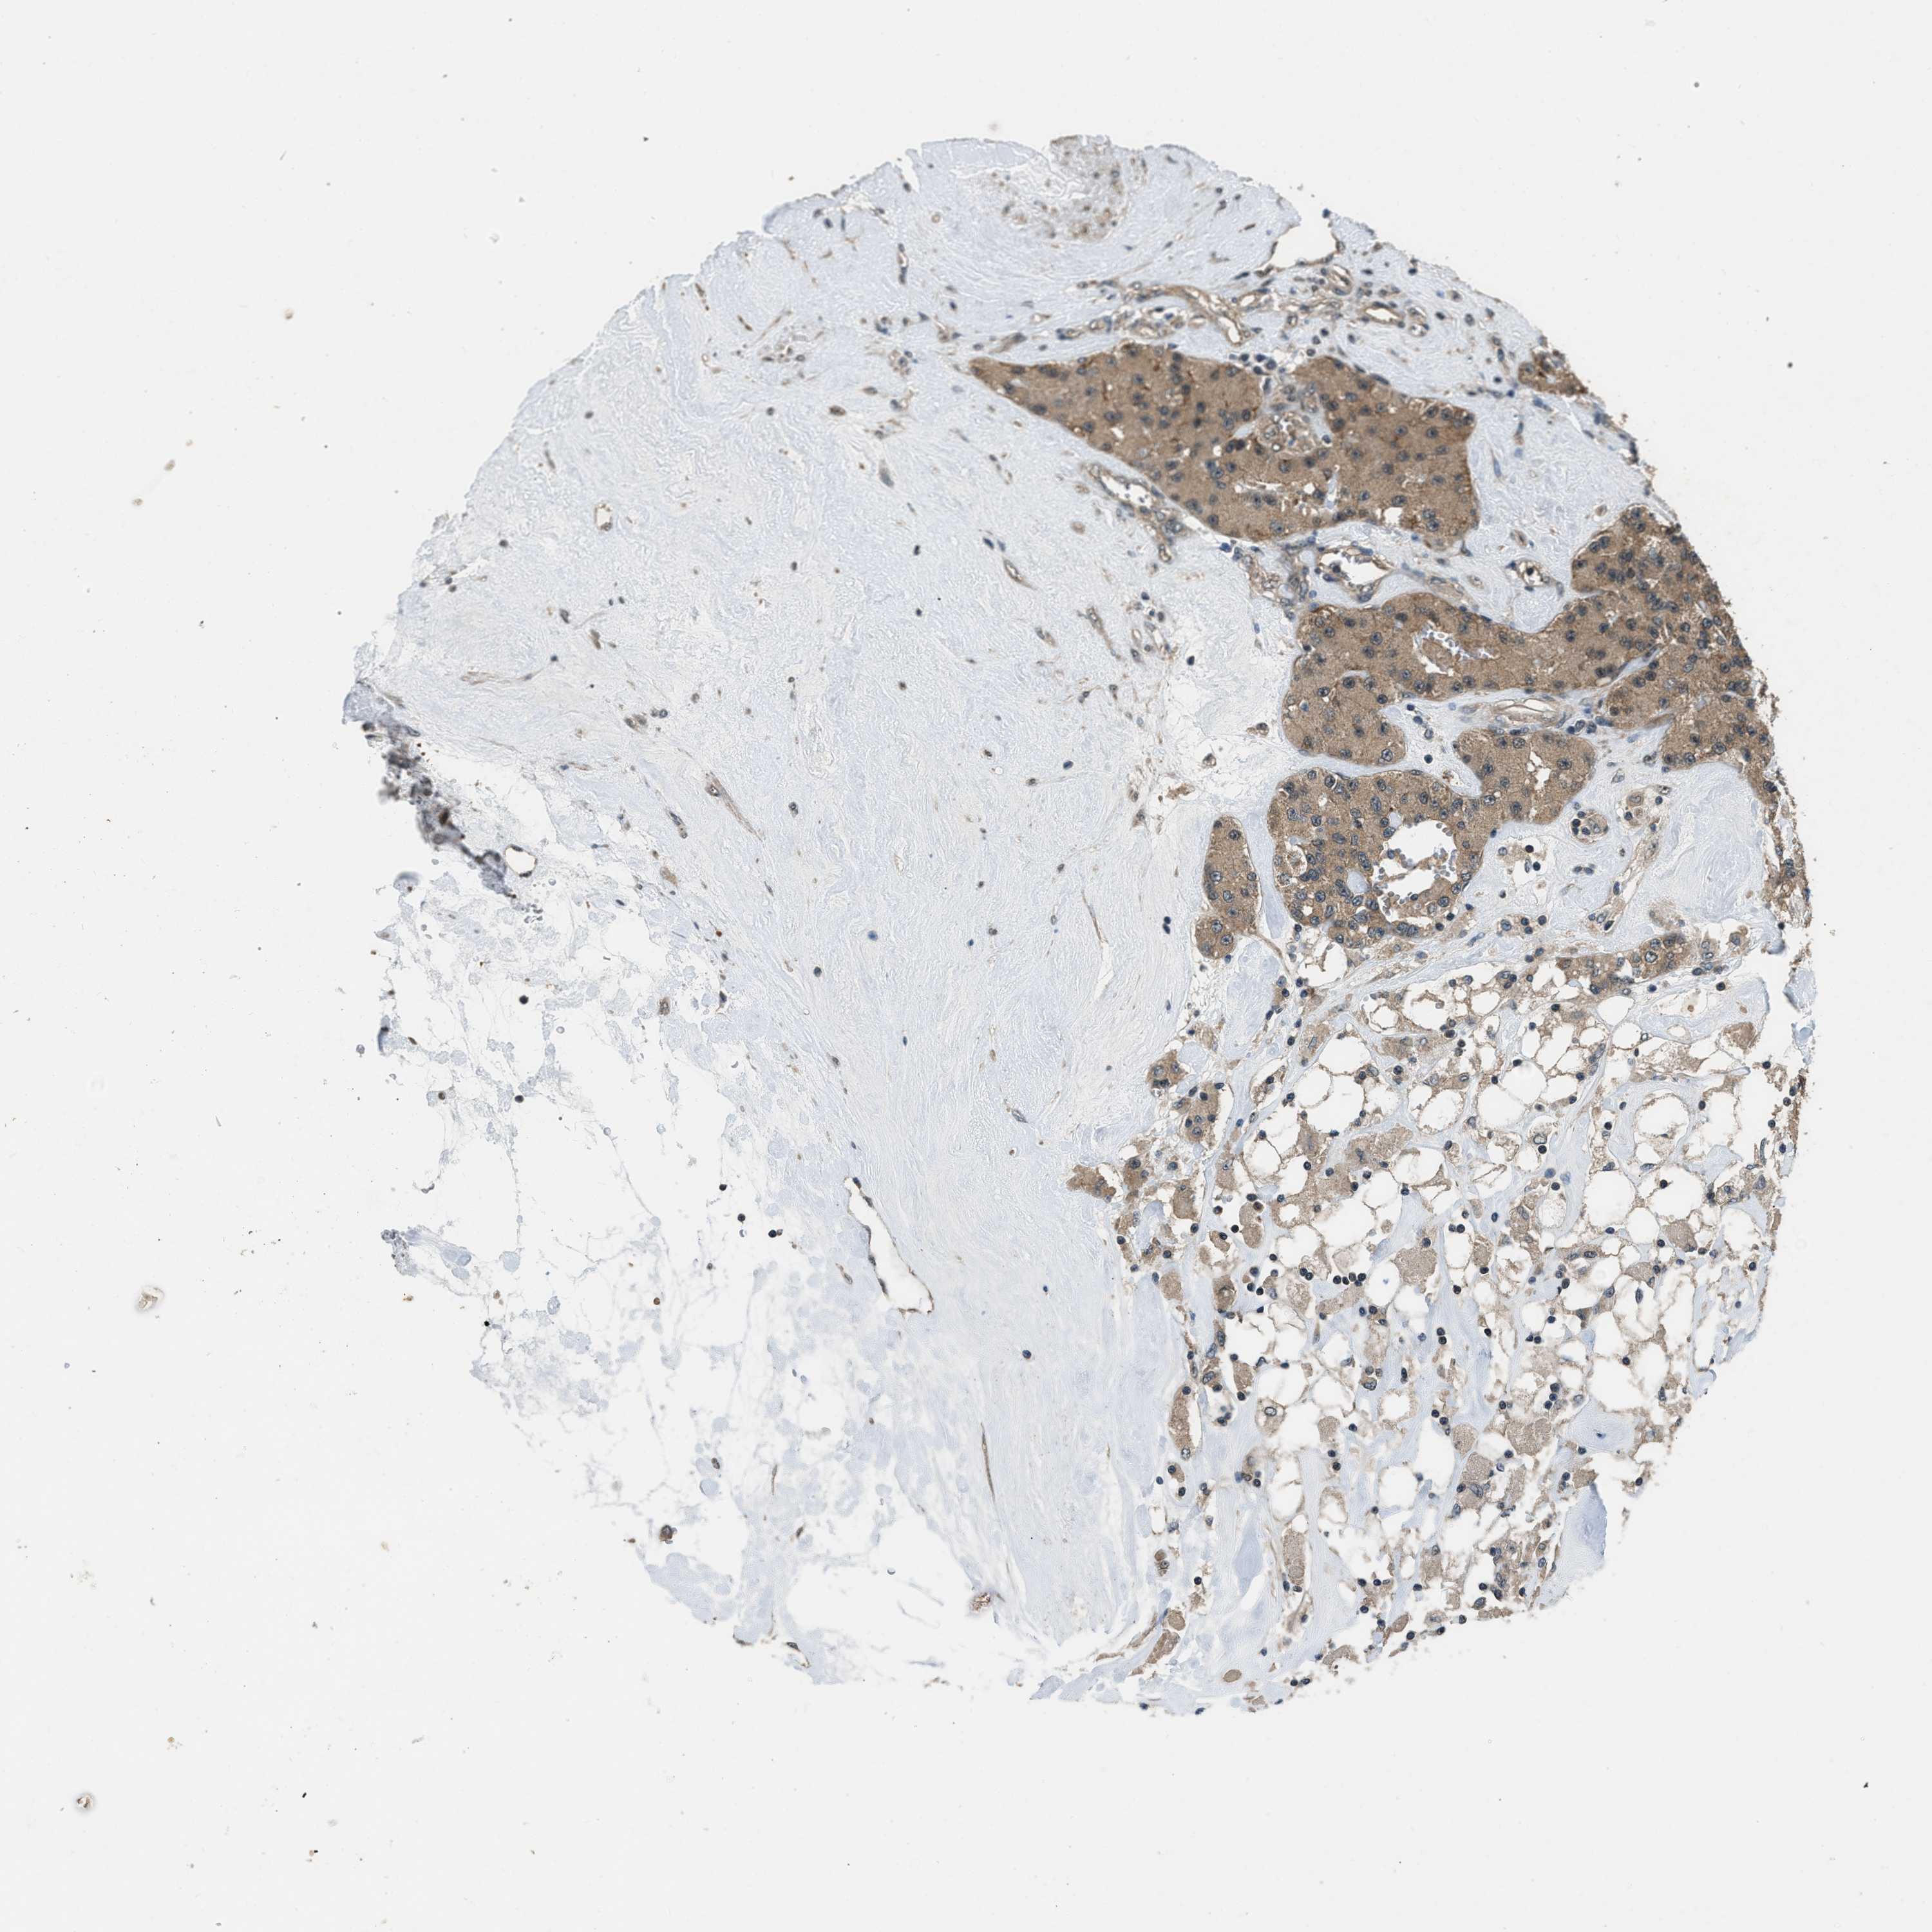

CARCINOID - Protein expressioni

A mouse-over function shows sample information and annotation data. Click on an image to view it in a full screen mode. Samples can be filtered based on level of antibody staining by selecting one or several of the following categories: high, medium, low and not detected. The assay and annotation is described here.

Antibody staining in the annotated cell types in the current human tissue is reported as not detected, low, medium, or high, based on conventional immunohistochemistry profiling in selected tissues. This score is based on the combination of the staining intensity and fraction of stained cells.

Each image is clickable and will lead to virtual microscopy that enables deeper exploration of all samples and also displays staining intensity scores, fraction scores and subcellular localization as well as patient and tissue information for each sample.

Antibody HPA019528

Staining

High

Medium

Low

Not detected

Intensity

Strong

Moderate

Weak

Negative

Quantity

>75%

75%-25%

<25%

None

Location

Nuclear

Cytoplasmic/membranous

Cytoplasmic/membranous,nuclear

Carcinoid, malignant, NOS